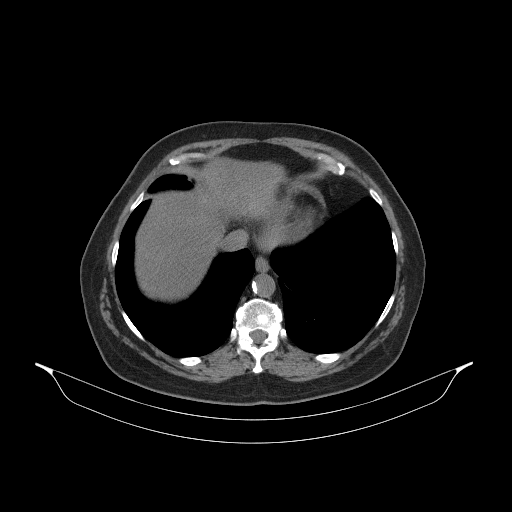

Slice 70 Targeting Evaluation

Slice: Slice_70

Conversion: NATIVE β†’ VENOUS

Targeted Slice 70 - Mediastinum Window Analysis (Generated vs Real Venous)

0.807

Mediastinum SSIM

37.0

Mediastinum RMSE

13.2

Mediastinum MAE

Average Mediastinum Window Metrics Across All Slices (85 slices) - Generated vs Real Venous

0.793

Mediastinum SSIM (Avg)

31.7

Mediastinum RMSE (Avg)

11.1

Mediastinum MAE (Avg)

Original VENOUS CT scan

No window - Raw intensity values